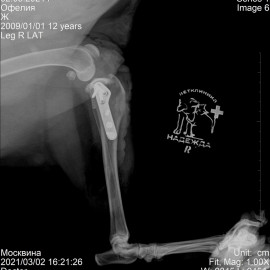

Наш пожилой , 11-ти летний, пациент породы лабрадор по кличке Офелия. Обратились в клинику " Надежда" с жалобами на хромоту на правую заднюю лапу после прыжка с высоты. После проведенных обследований собаке был поставлен диагноз: разрыв передней крестообразной связки правого коленного сустава. Была проведена операция TPLO.

Снимок 2 после операции